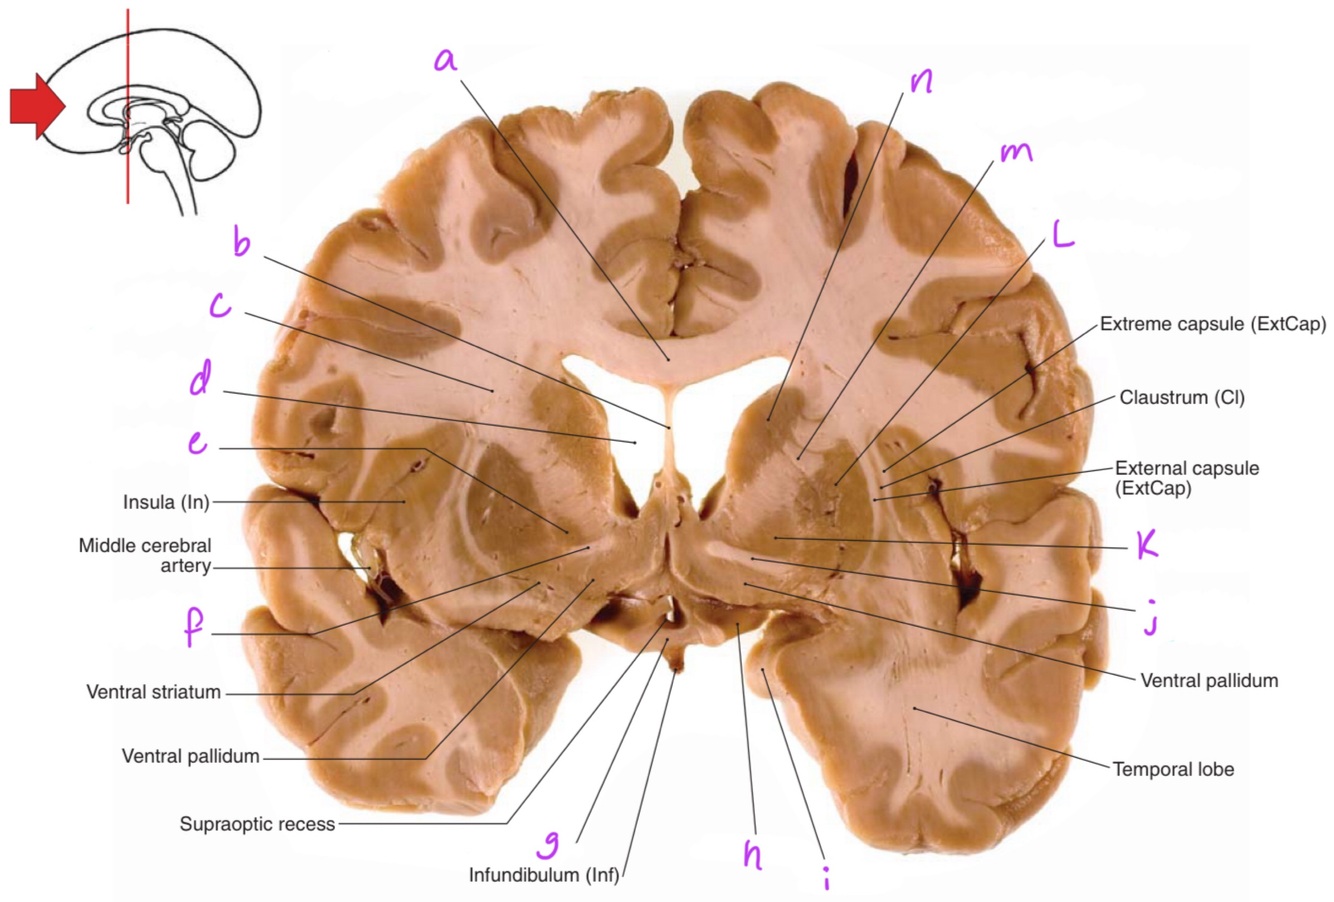

1

a

body of corpus callosum

2

b

Anterior horn of lateral ventricle

3

c

4

d

6

f

7

g

8

h

9

10

septum pellucidum

11

Corona radiata

12

13

e

Globus pallidus

14

Anterior commissure

15

Optic chiasm

16

Optic tract

17

i

Uncus

18

j

19

k

20

L

Putamen

21

m

Anterior limb of internal capsule

22

n

Head of caudate nucleus